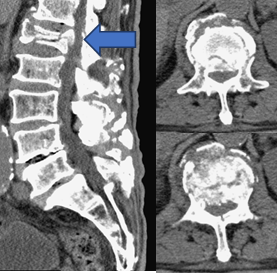

電腦斷層掃描(CT):比X光能更精確的看出骨頭的構造,所以更能判斷是否有骨折。另外,對於較高能量之骨折,可能影響到神經椎管造成神經壓迫,CT能夠看出椎管的形狀和大小,判斷是否造成神經壓迫。(圖三)

(圖三)